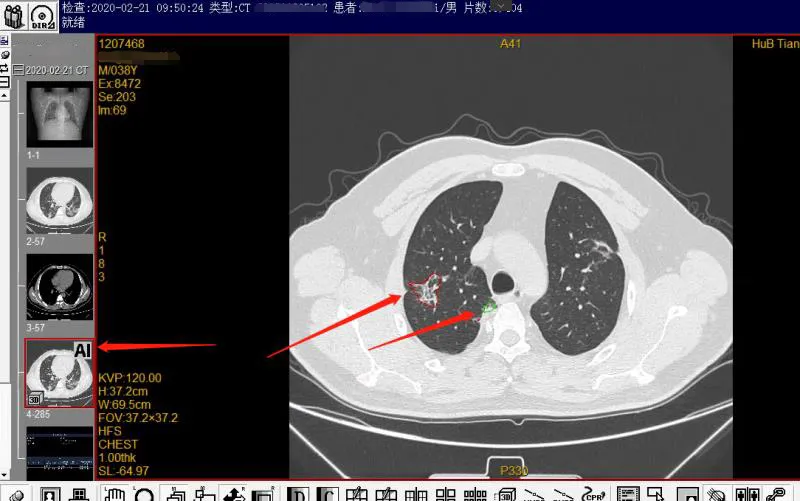

对新冠肺炎疑似患者进行早确诊、早治疗是阻止疫情蔓延,降低死亡率最为有效的方法。作为新冠肺炎防治主战场,天门一医积极引进蓝网科技与华为云联合研发的“新冠肺炎AI辅助筛查“系统。几百幅胸片几秒内即可完成筛查,并可同步给出辅助诊断和量化评估意见。对于疑似病例,系统会给出“疑似病毒性肺炎”以及疑似概率提醒,医生参考提示进行诊断审核并及时决定后续治疗措施。

通过AI的辅助,医生的诊断效率有了明显提升,单病例诊断耗时比以往平均缩短了数十分钟,大大缩短了患者的等待时间,对防止疫情进一步扩散起到了至关重要的作用。

智能AI检测出结果,大幅度缩短确诊时间